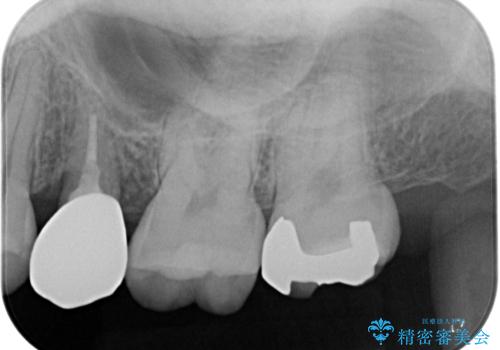

左上の七番目と六番目の歯と歯が接するところに虫歯をレントゲン上で確認できました。

噛み合わせが強く、以前にも当院で右上でゴールドインレーにより治療をされていたのでゴールドインレーにて治療しました。

ゴールドインレー(PGAインレー)はセラミックインレーと比べ、歯の切削量が少なく、適合性が著しくいいことが特徴です。上顎の奥歯は見えないので機能面でゴールドインレー、ゴールドクラウンはおすすめです。

違和感がないと喜んでいただきました。